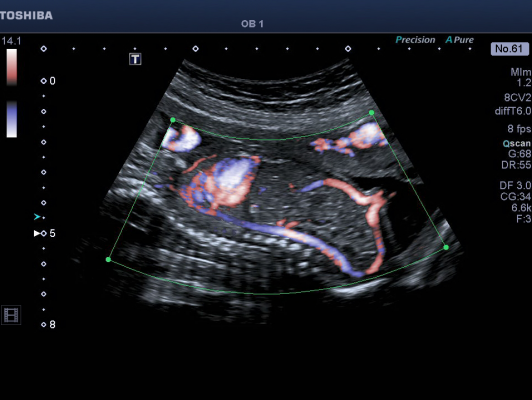

December 16, 2013 — Ultrasound will be able to depict blood flow with more detail and accuracy using Toshiba America Medical Systems Inc.’s work-in-progress ultrasound capability, which is the latest advancement to Toshiba’s Aplio 500 ultrasound system.

Despite advances in ultrasound, current imaging techniques struggle to detect microvascular blood flow in areas like the liver, kidneys, abdomen and lymph nodes because of limitatxions in conventional Doppler technologies. Toshiba’s technology will help solve this problem and current evaluations have shown promise in its ability to characterize tumors.

“The images we’ve produced so far with this technology are stunning,” said Forsberg. “It is able to clearly show low blood flow in small vessels throughout the body. The potential clinical utility for characterizing lesions, cysts and tumors could make ultrasound an even more important tool in diagnoses.”

“This level of vascular visualization combined with high frame rates is something we could not do before in ultrasound,” said Jiro Hata, M.D., Ph.D., professor, Department of Clinical Pathology and Laboratory Medicine, Kawasaki Medical School, Japan, and an early evaluator of this technology. “For example, ultrasound can now help with the evaluation of changing blood flow patterns, especially in the gastrointestinal tract.”